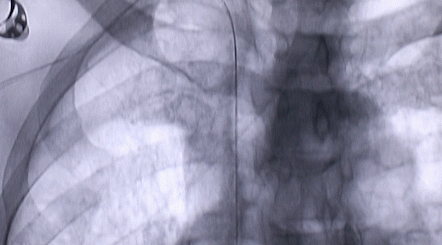

1月12日,西安國(guó)際醫(yī)學(xué)中心醫(yī)院心臟外科郭穎強(qiáng)主任團(tuán)隊(duì)成功為一名腹主動(dòng)脈閉塞、右側(cè)腎動(dòng)脈閉塞、左側(cè)腎動(dòng)脈重度狹窄、腹壁淺表動(dòng)脈側(cè)支循環(huán)形成、高血壓病3級(jí)(極高危組)合并閉塞性周圍動(dòng)脈粥樣硬化、急性腎功能不全的老年患者實(shí)施腎動(dòng)脈球囊擴(kuò)張 腎動(dòng)脈支架植入術(shù) 動(dòng)脈血栓抽吸術(shù) 髂動(dòng)脈開通術(shù),治好了困擾患者多年的頑固性高血壓。患者目前康復(fù)良好,將于近日出院。

患者張大伯今年74歲,一年前出現(xiàn)不明原因高血壓,最高血壓200/165mmHg,同時(shí)服用多種藥物效果不佳。禍不單行,近年來(lái)他時(shí)常感到腰背部酸痛,腹部常感飽脹不適,吃不下去飯。近兩個(gè)月,兩條腿也像是灌了鉛,抬不起來(lái),同時(shí)偶伴水腫。在當(dāng)?shù)蒯t(yī)院就診,服用多種藥物均不見好轉(zhuǎn),行主動(dòng)脈CTA,檢查提示發(fā)現(xiàn)腹主動(dòng)脈閉塞,兩條腎動(dòng)脈——右側(cè)閉塞、左側(cè)狹窄,閉塞性周圍動(dòng)脈粥樣硬化,腹壁淺表動(dòng)脈側(cè)支循環(huán)形成!

按照術(shù)前制定的方案,郭穎強(qiáng)主任和楊金保博士首先嘗試開通閉塞的右腎動(dòng)脈,但由于血栓機(jī)化、鈣化嚴(yán)重,右腎動(dòng)脈難以開通。遂謹(jǐn)慎擴(kuò)張狹窄的左腎動(dòng)脈,并成功植入一枚支架。之后經(jīng)過(guò)反復(fù)旋磨、抽吸,順利開通髂動(dòng)脈,但腹主動(dòng)脈閉塞段仍難以擴(kuò)通。此時(shí),患者居高不下的血壓很快恢復(fù)到正常水平。